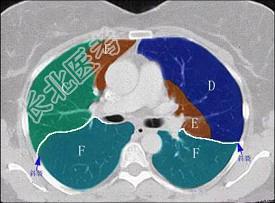

- 单项选择题结合肺段模式(见图),选出右肺下叶的组成 ( )

A、F

B、F+G

C、F+G+H

D、F+G+H+I

E、F+G+H+I+J